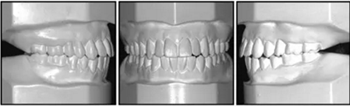

口內(nèi)相及模型:雙側(cè)磨牙、尖牙I類關(guān)系,良好的牙尖交錯(cuò)關(guān)系,覆合、覆蓋正常。